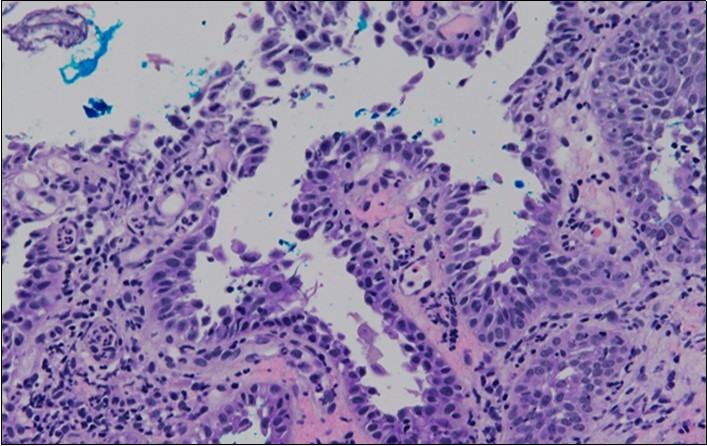

HPV test was negative for high risk subtypes of HPV. The punch biopsy specimen comprised a piece of inflamed cervical tissue in which the transformation zone was represented. The cervical tissue was covered by metaplastic and hyperplastic squamous epithelium showing intraepidermal suprabasal blister formation with acantholysis. Well vascularised dermal papillae lined residual basal cells giving rise to a tombstone appearance were present. There was no evidence of HPV, CIN, CGIN or invasive malignancy.

She was discussed at the hospital cyto-pathology conference to clarify the diagnosis. The original cytological smear specimen was reviewed, with features of bi-nucleation and koilocytosis consistent with LSIL. The cervical biopsy was also reviewed, confirming typical features suggestive of cervical pemphigus. (Figure 4a, Figure 4b, Figure 4c)

Figure 4a.Cervical tissue showing intraepidermal and supra-basal blister formation.

Figure 4b.Prominent acantholysis identified

Figure 4c.Well vascularised dermal papillae with residual basal layer giving rise to tombstone appearance